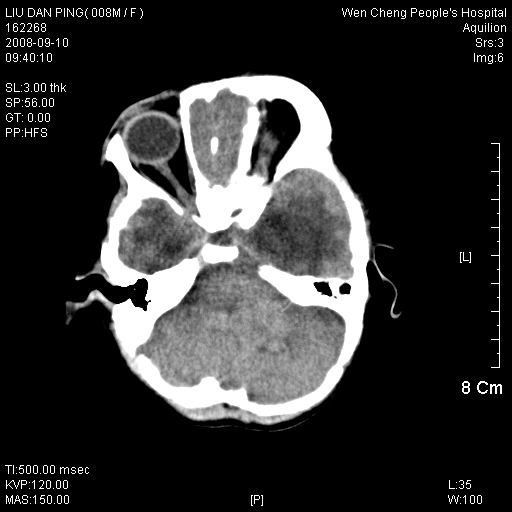

以下是引用卜一在2008-9-10 16:21:00的发言:[br]髓母细胞瘤伴梗阻性脑积水!支持![br]髓母细胞瘤特点:—般直径大于3.5cm,位于后颅凹中线之小脑蚓部。累及上蚓部的肿瘤延伸到小脑幕切迹之上,ct平扫肿瘤多呈均匀一致的高或等密度病灶,增强检查呈均匀一致的强化。病灶中有小坏死时,平扫亦可呈不均匀之混杂密度,注药后有增强。[br]

以下是引用zjzjr在2008-9-10 15:09:00的发言:[br]髓母细胞瘤伴梗阻性脑积水.